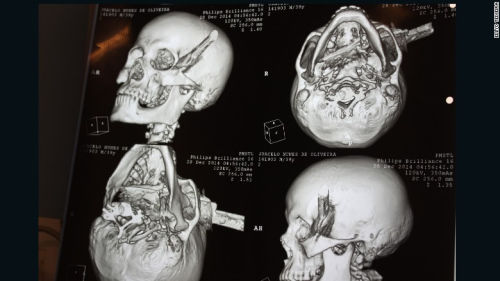

男子被人用刀刺中頭部,直穿頭骨。

中新網(wǎng)1月4日電 據(jù)外媒報(bào)道,巴西一名男子在與他人爭吵過程中被人用刀刺中頭部,直穿頭骨。在經(jīng)過2個(gè)半小時(shí)的手術(shù)后,該男子奇跡存活。

據(jù)報(bào)道,39歲受害男子系一名出租車司機(jī),事發(fā)時(shí)他正在一個(gè)酒吧喝酒,結(jié)果與人發(fā)生口角。男子被刺中4刀,其中3刀刺中身體,1刀被插進(jìn)頭部,橫穿過左眉骨。

男子在送醫(yī)途中還被耽擱了3個(gè)多小時(shí)。醫(yī)生說,刀插在頭上超過3小時(shí),男子還渾然不知,醫(yī)生分析可能是因?yàn)槟凶雍攘司频木壒省?/p>

醫(yī)生說,刀已經(jīng)完全穿過了男子的頭部,幾乎就要接近嗅覺神經(jīng),但僅僅破壞了部分味覺神經(jīng)。男子幾乎就要失去視覺、嗅覺和味覺,但是沒想到,幸運(yùn)的是他將毫發(fā)無損。